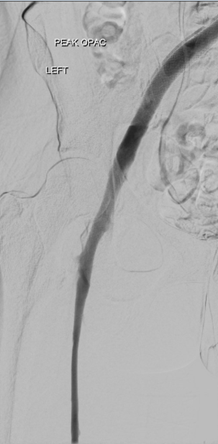

Venograma de la pierna izquierda donde se muestra un trombo oclusivo en las venas profundas más visualizadas.